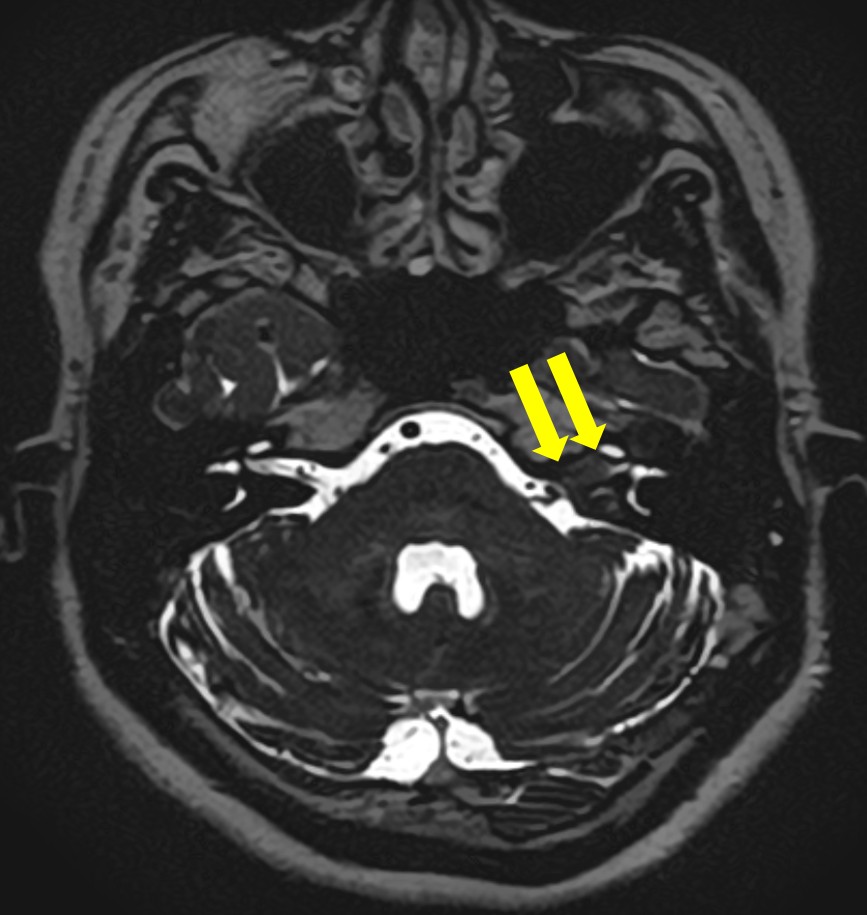

聴神経腫瘍・症例画像

反対と比べると黒く(低信号)なっているのが一目瞭然